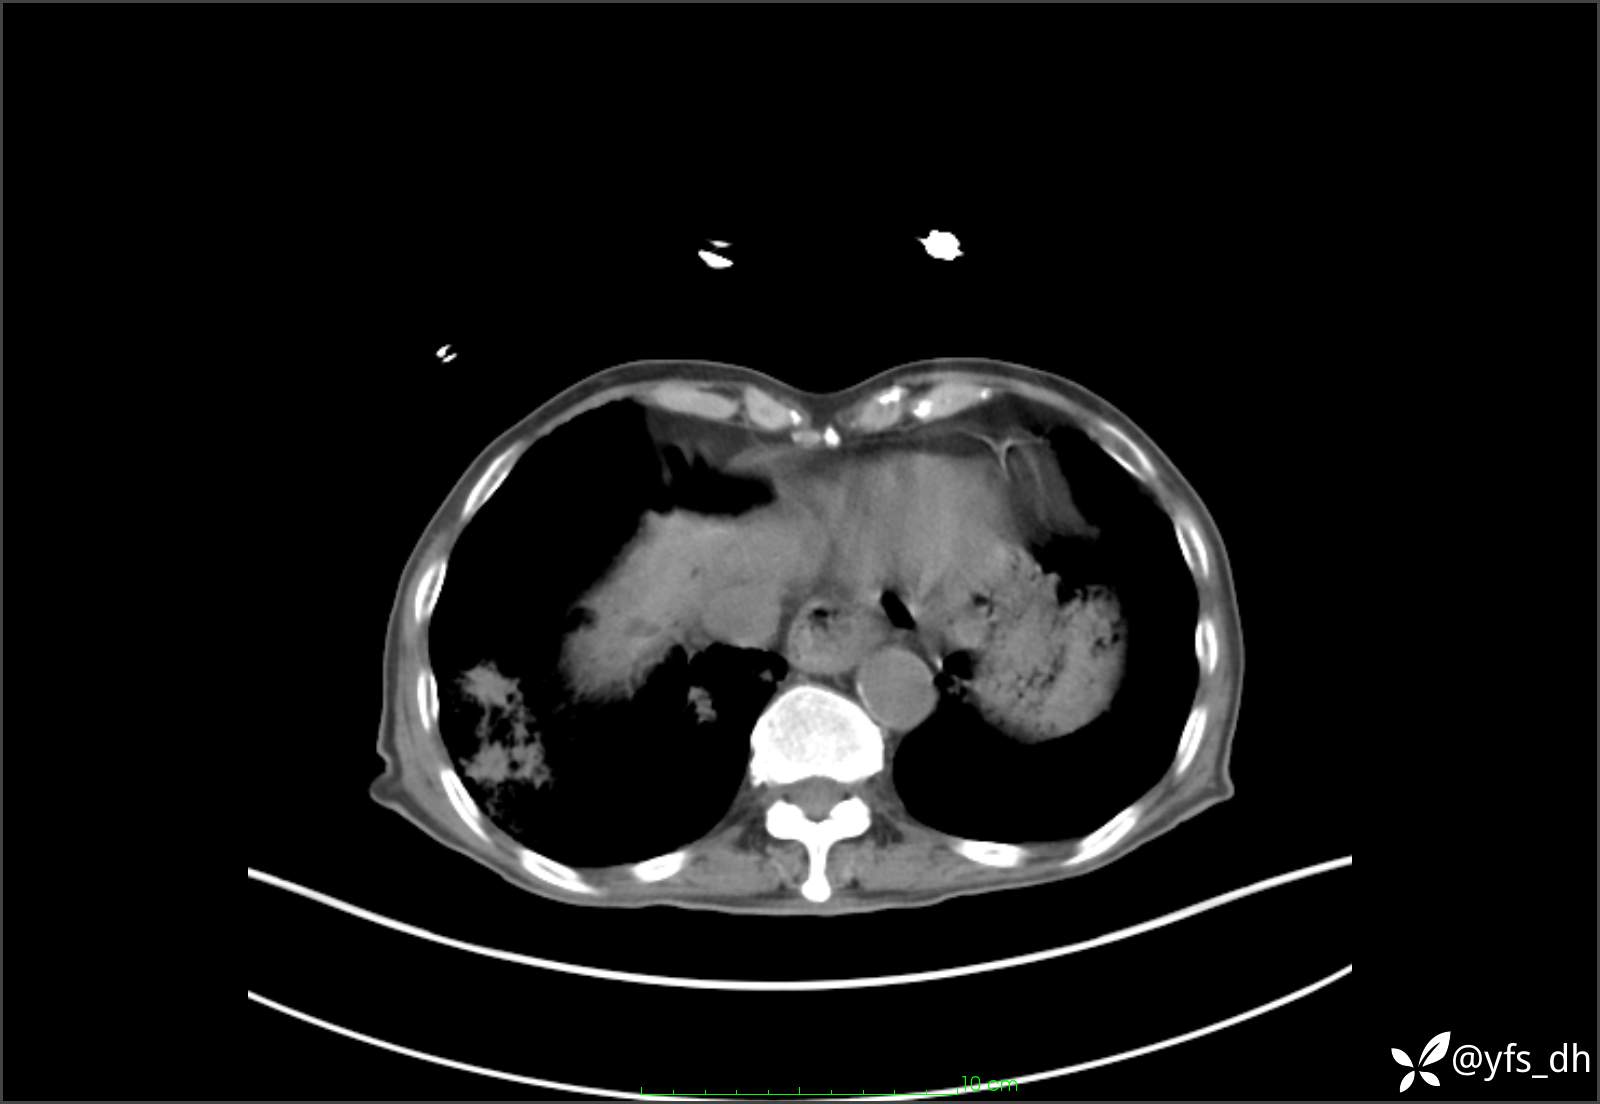

1.简要病史:患者4天前突发上腹部疼痛不适,但可以忍受。3小时前饭后突然加重,不能忍受后就诊。

2.简要手术记录:术中见腹盆腔大量肠液及粪便,乙状结肠中下段见一约3cm的破口。